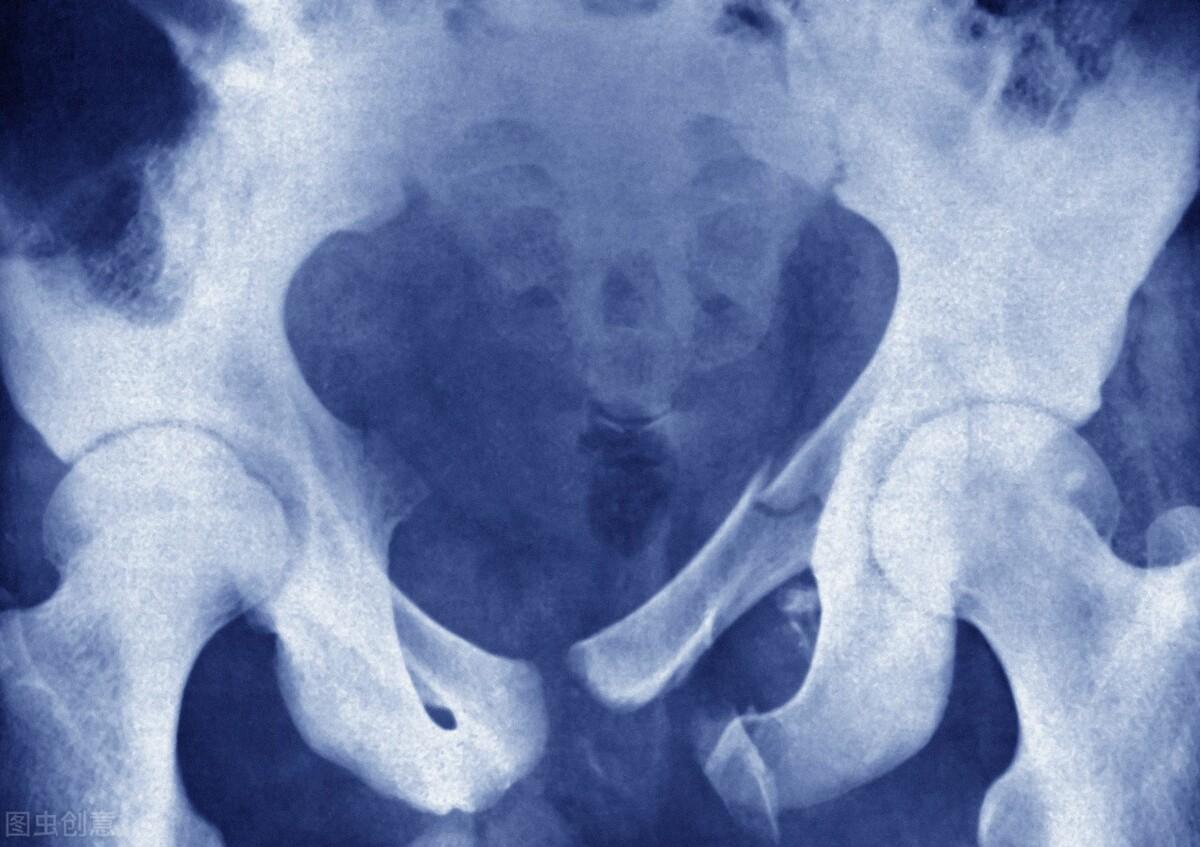

骨盆骨折属于临床上一种比较常见的骨外伤,主要是由于直接暴力和间接暴力引起的,占骨折总数的1%~3%左右。在骨盆骨折之后,很多患者会出现一些合并症,所以在骨折之后,必须要立刻进行现场救护,提高骨折患者的治愈率。

骨盆骨折之后进行现场救护,要注意以下几点:首先就是要提前准备担架,不能让患者自己走动,也要避免搬动患者的频率,否则会对骨折的患者身体的神经或者是血管造成第2次损伤。然后要检查患者的呼吸道是否通畅,如果患者呼吸道不通畅的话一定要及时进行呼吸道堵塞处理,同时观察是否有其他的异常症状。由于患者是骨盆部位骨折,所以要用大布或者是三角巾把骨折的部位包扎好,并且让患者以屈膝平卧的姿势躺在担架上。

骨盆骨折之后能不能下地,要根据患者恢复情况判断。针对一些骨盆部位出现骨折情况的患者来说,如果骨折部位还不太稳定的话是不能够下地活动的,一般骨折的患者要经过两个月左右的时间才能够完全下地。如果骨盆骨折的患者过早的下地活动的话,可能会使得骨折的部位出现再次移位的情况,或者是使得患者骨折部位出现无法愈合或愈合时间过长,比较轻微的症状就是使得骨折部位肿胀或者是疼痛的症状加重。同时由于下地时骨盆会受到较大的压力,所以在没有完全痊愈之前患者是不能够下地的。

骨盆骨折的患者损伤往往比较严重,在治疗之后还需要密切观察患者的各项生命体征,防止失血性休克发生,另外还需要积极的进行补液治疗。无论保守治疗还是手术治疗,患者都必须要卧床休息,避免过多的活动。同时还应该密切观察肢体远端的皮肤和血运,出现任何异常及时治疗。